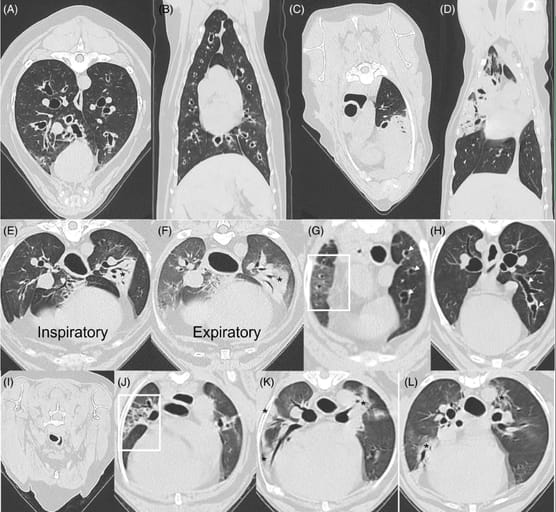

Use of thoracic computed tomography to aid in classification of final diagnosis in dogs with respiratory disease based on airway, parenchymal or mixed airway and parenchymal involvement. (A, B) Transverse and dorsal sections from a 6-year-old MC Siberian Husky with airway disease. Note the marked peribronchovascular thickening creating an appearance of peribronchial cuffing in cross-section. Bronchiectasis was noted by dilatation and lack of tapering of airways traversing to the periphery. The final diagnoses were eosinophilic bronchitis and bronchiectasis. (C, D) Transverse and dorsal sections from a 10-year-old FS Labrador retriever with parenchymal disease. Note the extensive regions of consolidation. Histology and response to immunosuppression confirmed an immune-mediated lung disease. (E, F) Paired ventilator-assisted inspiratory: expiratory breath hold transverse sections from an 11-year-old MC French bulldog with both airway and parenchymal disease substantially contributing to clinical signs. On the inspiratory series, increased peribronchovascular thickening and focal consolidation (*) are noted. On the expiratory series, the caliber of the segmental and subsegmental airways are smaller than on the inspiratory series with a corresponding loss of lung volume and presence of more global ground glass opacity because of downstream effects of bronchomalacia. The previously noted region of consolidation (*) remains present. The final diagnoses included brachycephalic obstructive airway syndrome, bronchomalacia, aspiration pneumonia, and suspect pulmonary fibrosis (corresponding lesions not shown). (G, H) Transverse images from a 13-year-old FS French bulldog with predominating airway lesions and mild, focal evidence of parenchymal disease. In (G), ground glass opacification in the mid-zone of the lung (within the white box), with Hounsfield units ranging from −425 to −550. The white arrows on the right side of the figure show bronchiectatic airways. Further evidence of cylindrical bronchiectasis is seen in (H) with a lack of tapering as shown by the white arrows. Using data from the clinical picture and other advanced diagnostics, the final diagnoses were chronic bronchitis, bronchiectasis, mainstem bronchial collapse, hiatal hernia, and uncharacterized parenchymal disease. (I-L) Transverse images from a 14-year-old FS Pomeranian with predominating parenchymal disease and a lesser contribution of airway disease. In (I) taken from the expiratory series, grade II tracheal collapse is demonstrated by a 50% reduction in luminal diameter with a flattened shape. In (J), the box outlines a region of architectural distortion characterized by traction bronchiectasis/bronchiolectasis superimposed on a background of reticulation and ground glass opacity, compatible with pulmonary fibrosis. In (K) and (L), there are multifocal regions of ground glass opacity and consolidation (*). Final diagnoses were grade II tracheal collapse, grade I mainstem bronchial collapse, grade I bronchomalacia, extra-esophageal reflux, suspect pulmonary fibrosis, and uncharacterized parenchymal disease.